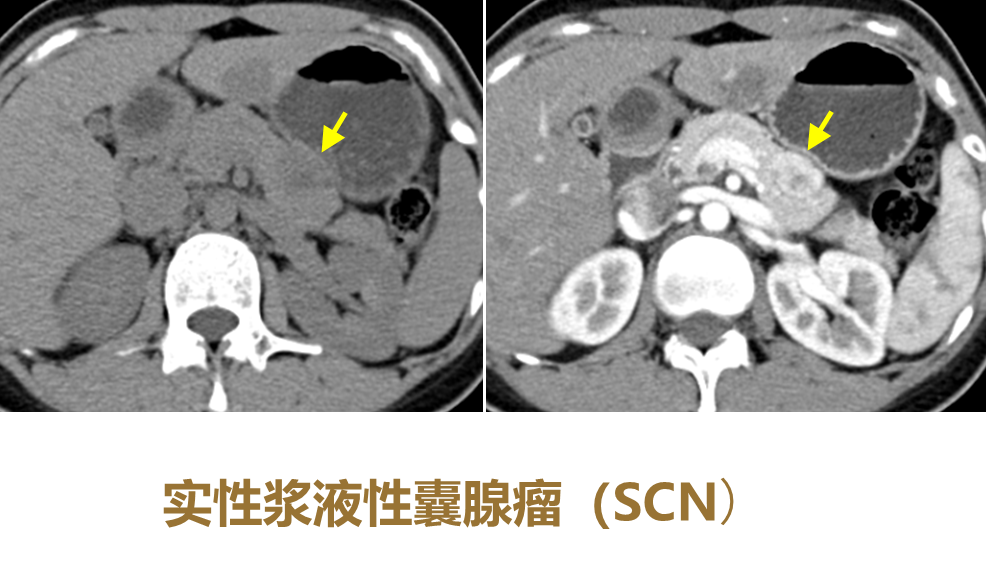

CT平扫:病灶内钙化

图7 浆液性囊腺瘤(SCN)CT平扫显示病灶中央钙化

(图片来源:余日胜教授讲课使用)